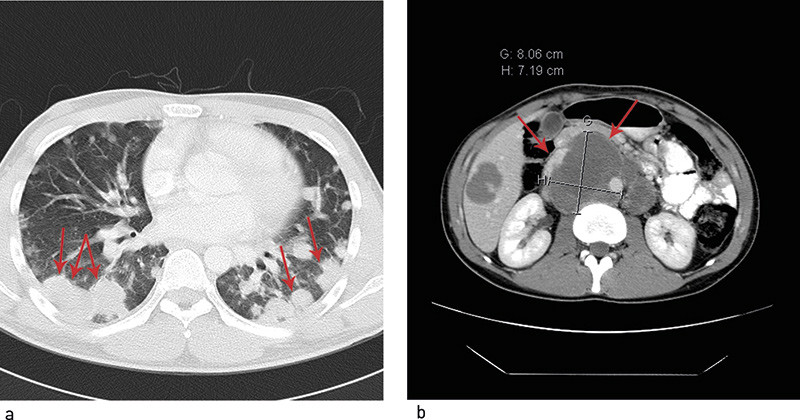

Pasienten utviklet nattesvette i så stor grad at sengetøyet ble gjennomvått og måtte skiftes. Han ble allment dårligere, fikk i tillegg brystsmerter og ble etter hvert innlagt på lokalsykehuset. CT viste et stort antall rundfortetninger i begge lunger, forandringer i lever, ekspansive prosesser paraaortalt samt forstørrede lymfeknuter i bekkenet. Det forelå tumormasser retroperitonealt, med største diameter 10 cm (fig 1). Han hadde sterke, opiatrefraktære brystsmerter og hadde takypné og lav O₂-metning. Han ble overført til intensivavdeling der det ble lagt inn epiduralkateter, med god symptomlindrende effekt. Han ble oppfattet som svært syk med utbredt kreftsykdom. Det ble derfor raskt tatt kontakt med tertiærsykehus med tanke på overflytting for videre utredning og behandling. Pasienten ble overført til dette sykehuset omkring ett år etter at han første gang søkte lege for mastalgi.

Fem måneder etter oppstart av kjemoterapi ble det utført bilateralt retroperitonealt glandeltoilette. Histologisk undersøkelse av resektatet viste nekrotiske metastaser og en liten rest av modent teratom. På dette tidspunktet hadde han normale tumormarkører, men over 50 resterende lungelesjoner. Han ble vurdert med tanke på torakotomi og reseksjon av restlesjoner. Operasjon var imidlertid utelukket da lesjonene gjennomgående var små (< 2 cm), og i et høyt antall. Ved gjentatte bildekontroller var det tilbakegang av lungeforandringene, som ble oppfattet som sannsynlig ikke-viabelt restvev med lavt opptak ved FDG-PET-undersøkelser (fig 2).